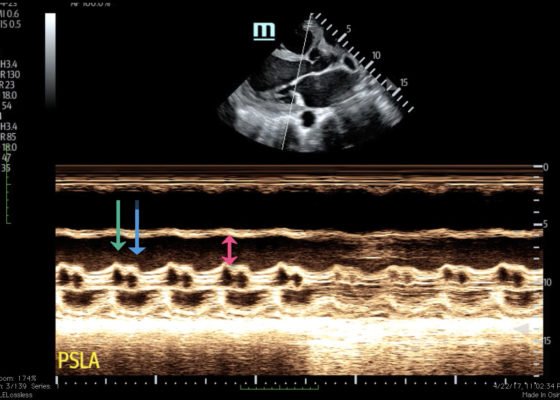

DOI: https://doi.org/10.21980/J8HD1RBedside ultrasound with the phased array probe was used to obtain a parasternal long axis view which demonstrated poor contractility and a severely decreased ejection fraction (EF). M-mode was placed over the anterior leaflet of the mitral valve to create a tracing depicting both the E-wave of early diastole (green arrow) and the A-wave from the atrial kick (blue arrow). The shortest distance between the septum and the mitral valve on the M-mode tracing gives the patient’s E-Point Septal Separation (EPSS) (pink arrow). EF can be estimated using the formula EF=75.5-2.5 x EPSS (in mm). This patient’s EPSS was measured to be 20mm which estimates that she had an EF of 25.5%.